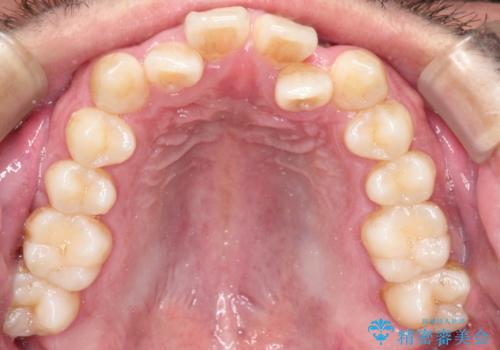

患者様がマウスピースを希望されていましたが、上の前歯のがたつきを先にワイヤーで改善する方が早く治療が終了することが可能であるとお伝えし、上顎のみ半年間ワイヤーで治療を行いました。

マウスピースのみでの治療も可能でしたが、治療期間がもう少し延長していた可能性があります。

器具や治療方法についても、矯正治療の前にしっかり相談させていただきます。